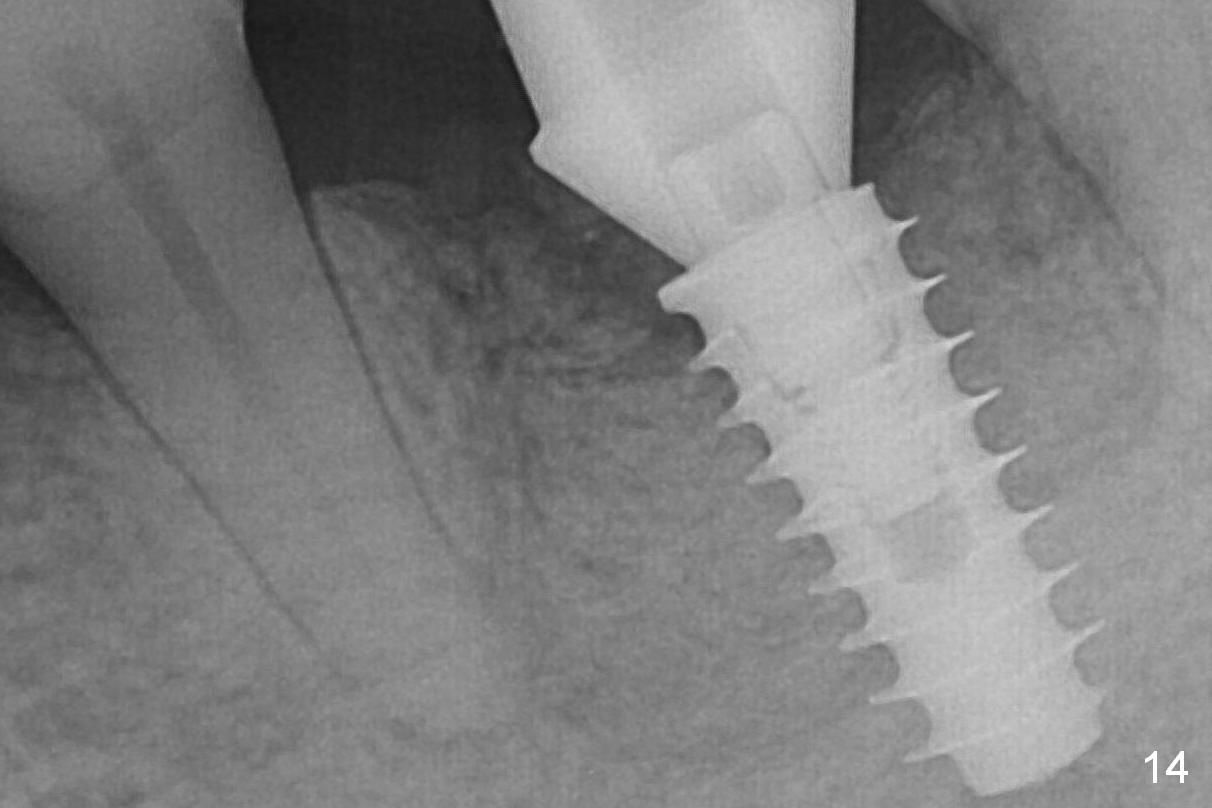

There is a new pattern of bony trabeculae around the implant 4.5 months postop (Fig.14). Bone density increases 1 year 4 months post cementation (Fig.15).